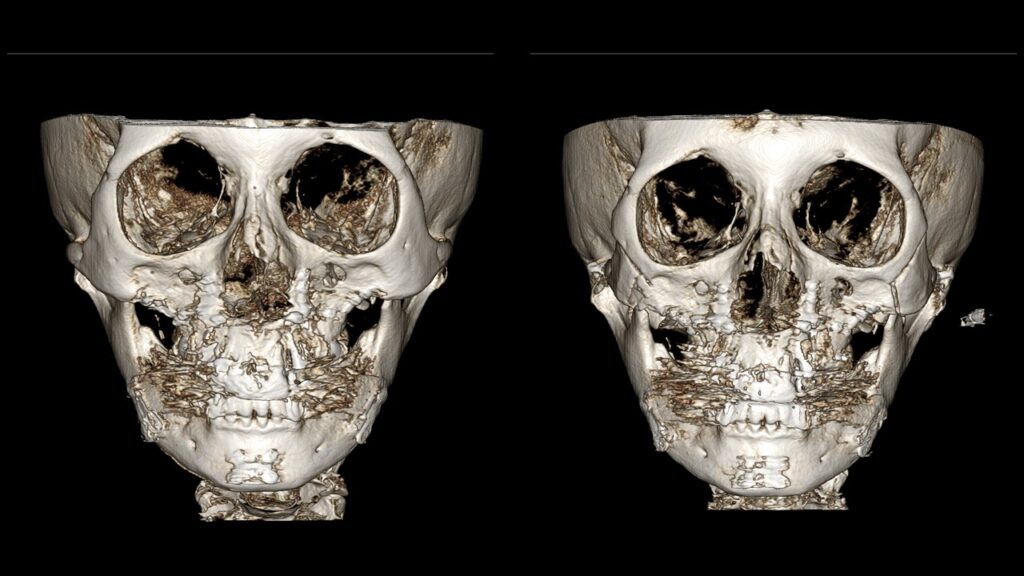

4. Case Studies (3DCT & Medical Photos)

-

Case 1: (Zygoma Reduction + Face Lift) 1-year post-op shows a significant reduction in mid-face width and improvement in nasolabial folds.